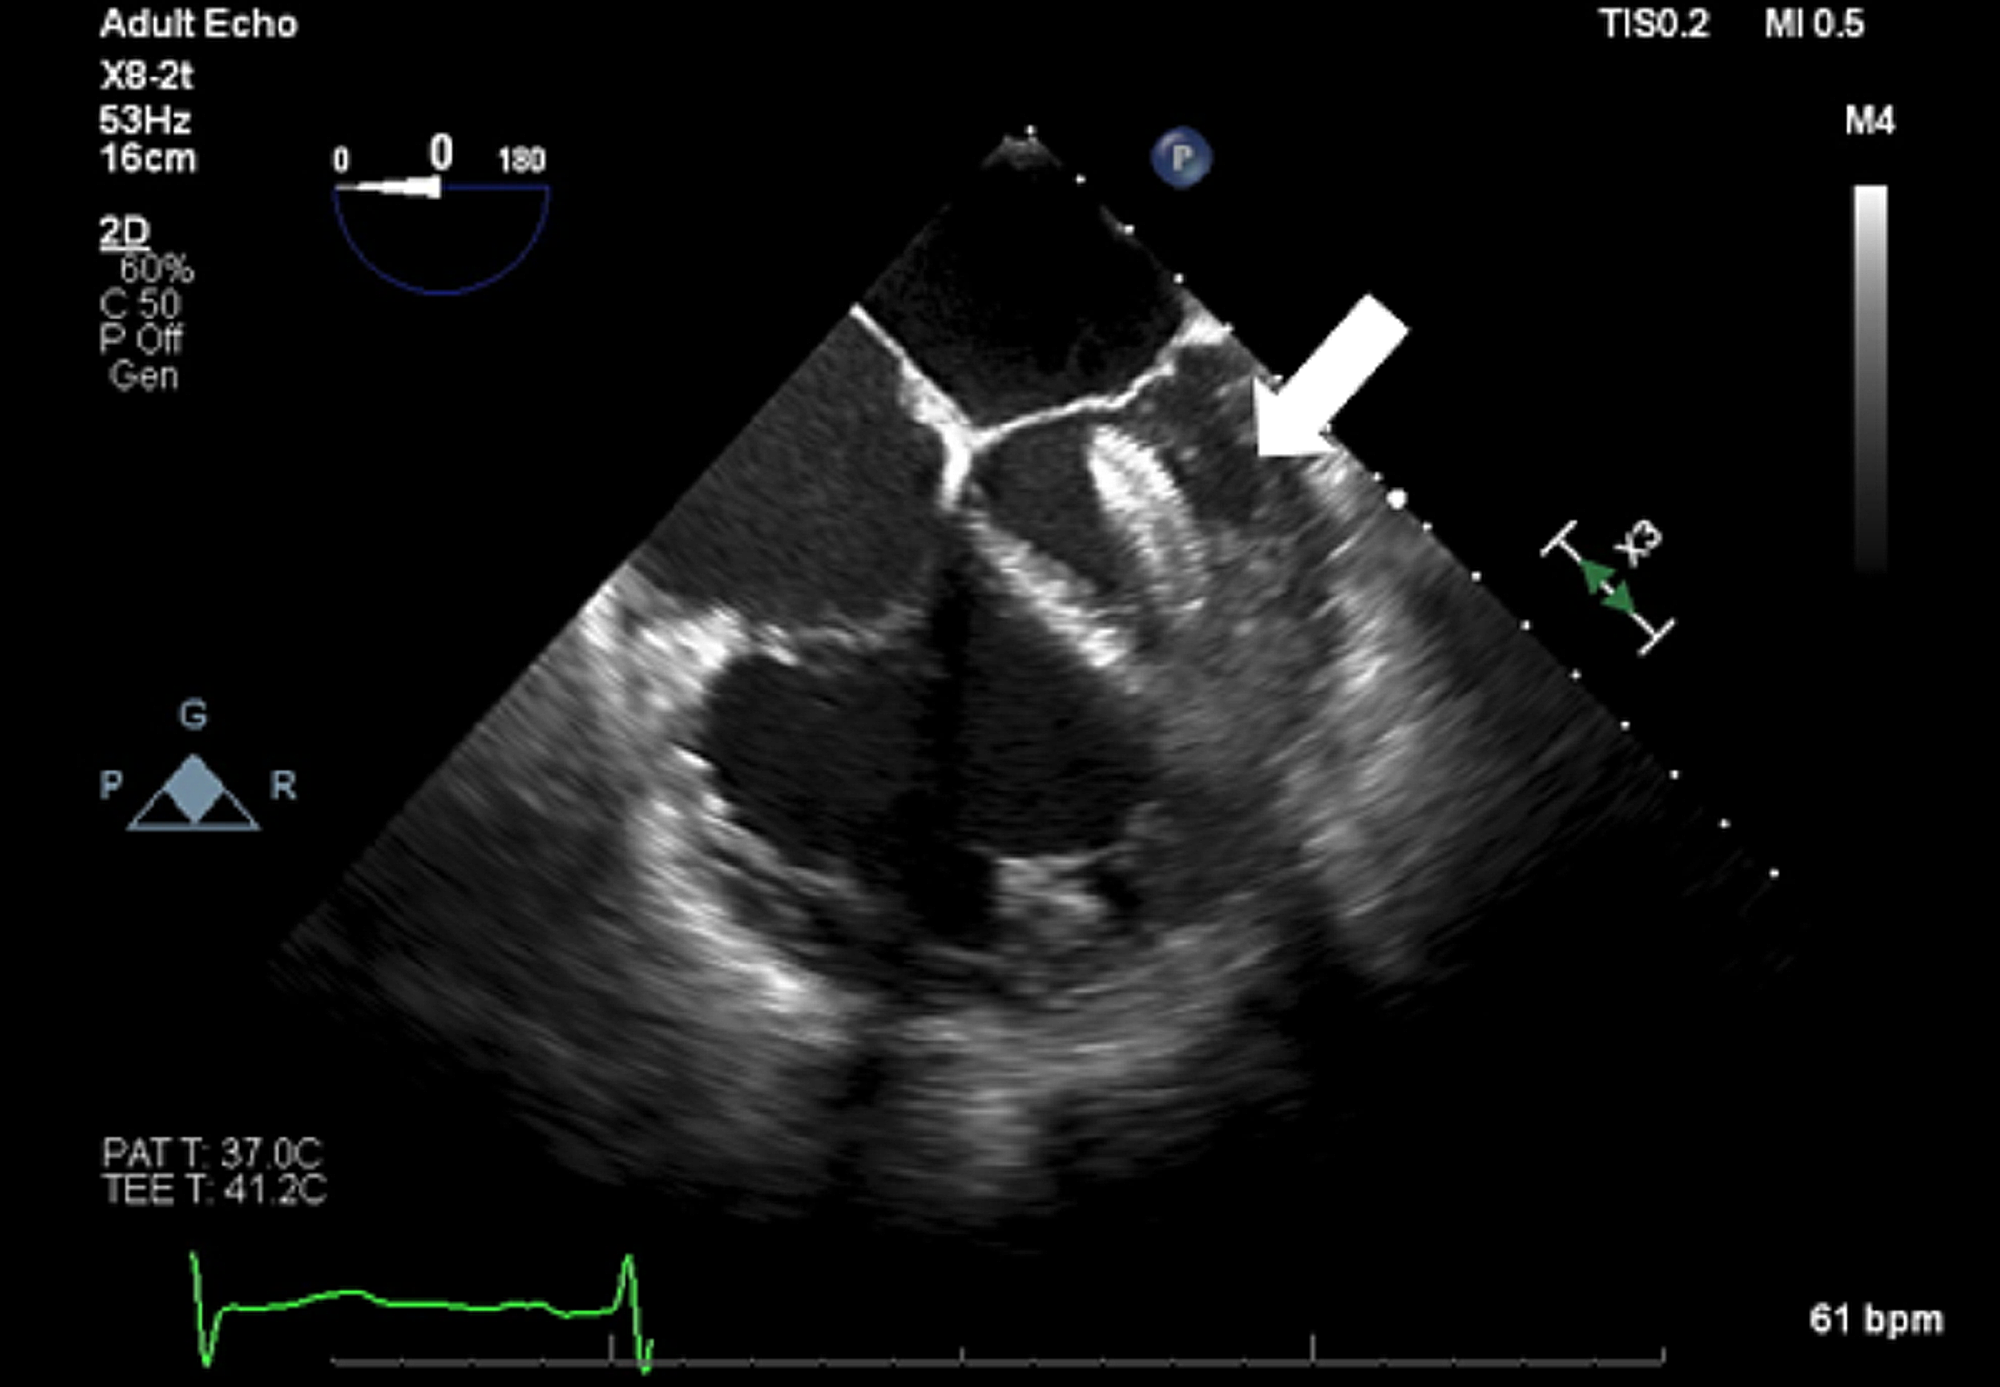

Figure 2 from Anesthetic management of Amplatzer atrial septal defect

Figure 1 from Anesthetic management of Amplatzer atrial septal defect Asd Closure Device Embolization The most common complications associated with an asd occluder device appear. Device closure of an asd is an attractive and safe option; Device closure of an asd is an attractive and safe option; Device embolization is a potential complication of every attempted asd closure, and the causative factors can be undersized. However, it may be associated with certain adverse events. Asd Closure Device Embolization.

Figure 2 from Anesthetic management of Amplatzer atrial septal defect Asd Closure Device Embolization However, it may be associated with certain adverse events like device embolization. See clinical datasee why dose matters Device closure of an asd is an attractive and safe option; The most common complications associated with an asd occluder device appear. Device closure is now considered the standard of care for secundum asds in most institutions worldwide, and allows many patients. Asd Closure Device Embolization.